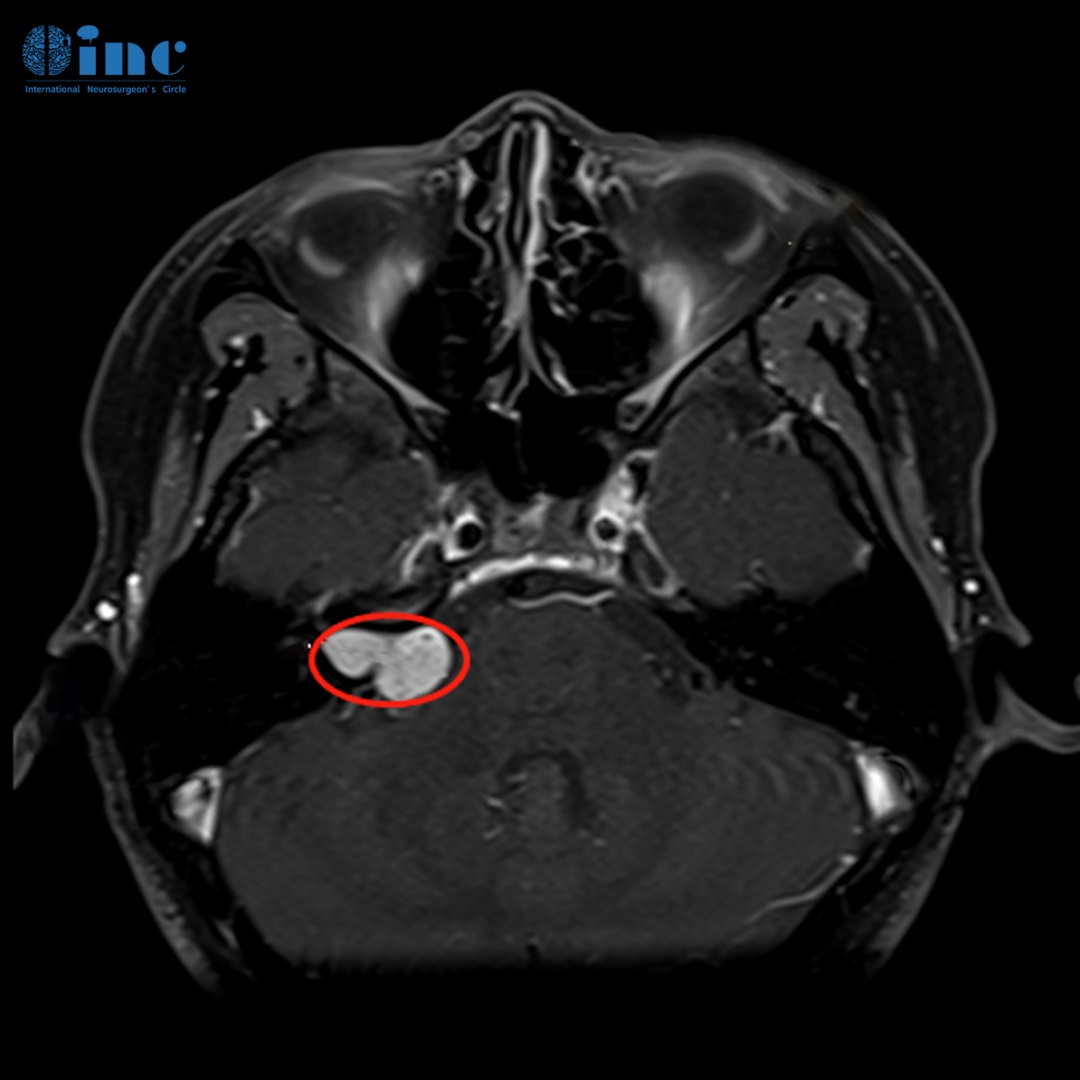

聽神經瘤MR

術前MR:姜女士顱腦MR提示聽神經瘤病變,瘤體約2cm大小,但是有一部分完全生長于內聽道骨質,壓迫面聽神經。